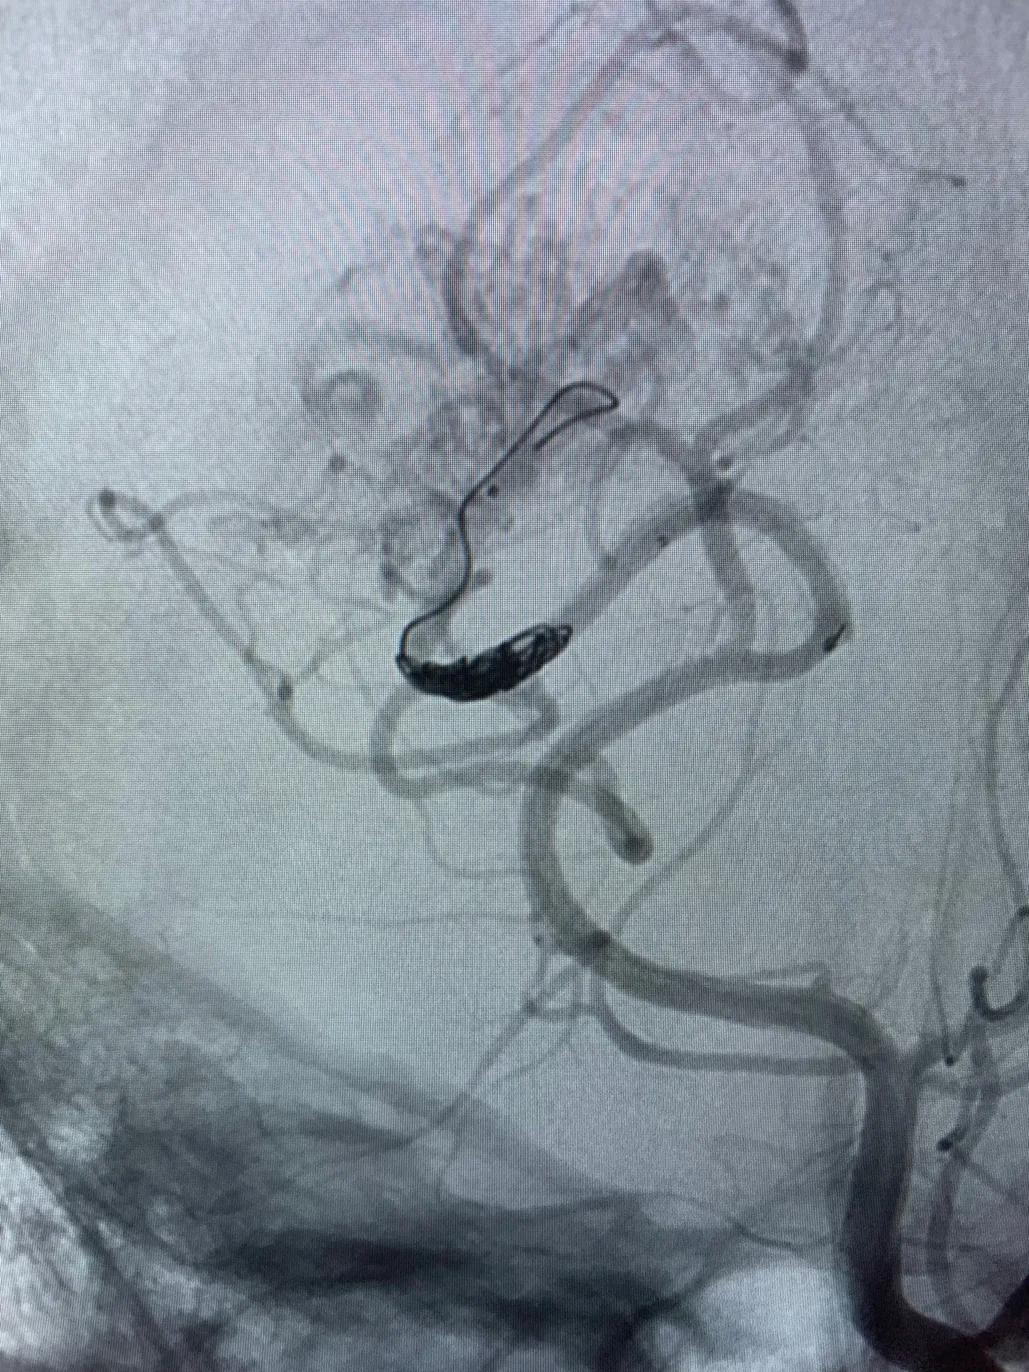

高压锅技术(Pressure Cooker Technique,PCT)是指在使用可解脱微导管进行Onyx栓塞时,在其可解脱点和导管远端之间,用另一根微导管(较细血管使用Magic,较粗血管使用10系列微导管)注射弹簧圈或nBCA等形成塞子,阻止Onyx返流,实现更好的栓塞效果。